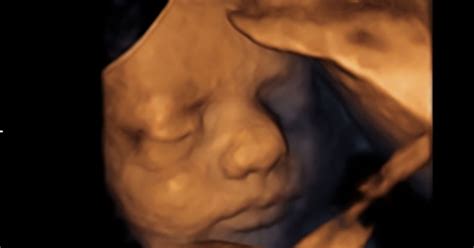

Spontani splav, znan tudi kot izguba nosečnosti pred 20. tednom, je žalostna, a razmeroma pogosta izkušnja, ki prizadene med 10 in 20 odstotkov vseh znanih nosečnosti. Dejansko število je verjetno še višje, saj se številni spontani splavi zgodijo tako zgodaj v nosečnosti, da ženska sploh ne ve, da je noseča. Kljub temu, da je spontani splav pogost, to dejstvo ženskam ne olajša soočanja s to izgubo. V večini primerov se spontani splav zgodi, ker se plod ne razvija po pričakovanjih ali kot bi se moral.

Približno 50 odstotkov vseh spontanih splavov v prvem trimesečju nosečnosti (do 13 tednov) povzročijo kromosomske nepravilnosti. Kromosomi so drobne strukture v celicah, ki nosijo naše gene. Ti geni določajo vse telesne lastnosti, od spola do barve las in oči. Med oploditvijo se združita dva sklopa kromosomov. Če ima jajčece ali semenčica nenormalno število kromosomov, bo tudi zarodek imel nenormalno število. Med rastjo zarodka, ko se celice delijo, se lahko pojavijo nadaljnje nepravilnosti, ki vodijo do spontanega splava. Večina teh kromosomskih težav nastane po naključju in ni podedovana od staršev.